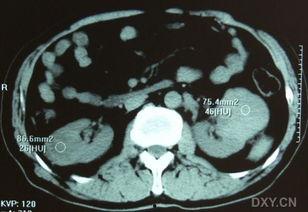

拿到双肾B超视频后,接下来就是解读环节了。医生会根据视频中的图像,分析肾脏的大小、形态、位置以及内部结构,从而判断是否存在异常。

一般来说,双肾B超视频会关注以下几个方面:

1. 肾脏大小:肾脏的大小与年龄、性别等因素有关。如果肾脏大小异常,可能是肾脏疾病的表现。

2. 肾脏形态:肾脏的形态应该是光滑、对称的。如果出现肿块、囊肿等异常,就需要进一步检查。

3. 肾脏位置:肾脏的位置应该在腰部两侧,如果位置异常,可能是肾脏下垂等疾病的表现。

4. 内部结构:肾脏内部结构包括肾皮质、肾髓质等。如果出现异常,可能是肾脏疾病的表现。